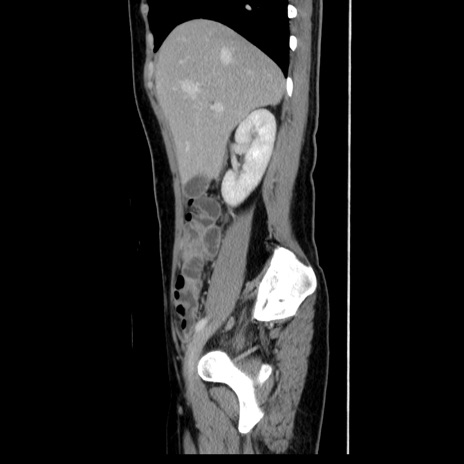

症例39(矢状断像)

【症例】40歳代女性

【主訴】上下腹部痛

【現病歴】2日目から下腹部痛あり。夜間は痛みで眠れなかった。昨日より上腹部痛と下痢が出現。臥位で痛みは軽快したため、休んでいた。本日になって臥位でも立位でも痛みが強くなってきたため救急要請。

【既往歴】子宮内膜症

【身体所見】部:平坦・軟、左上下腹部に圧痛あり、反跳痛あり。

【データ】WBC 21800、CRP 26.78

CT